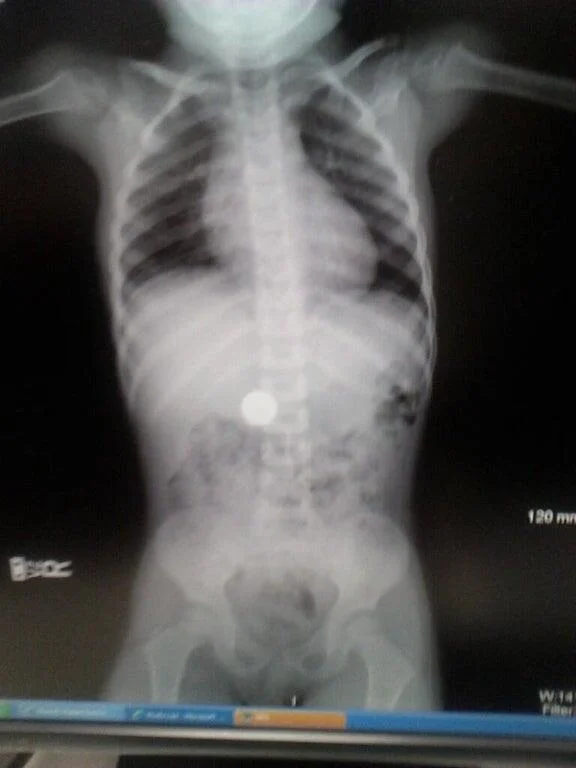

12. Как выглядит детская глупость

Этой мой рентгеновский снимок, который сделали после того, как я украл у брата монетку и проглотил её.